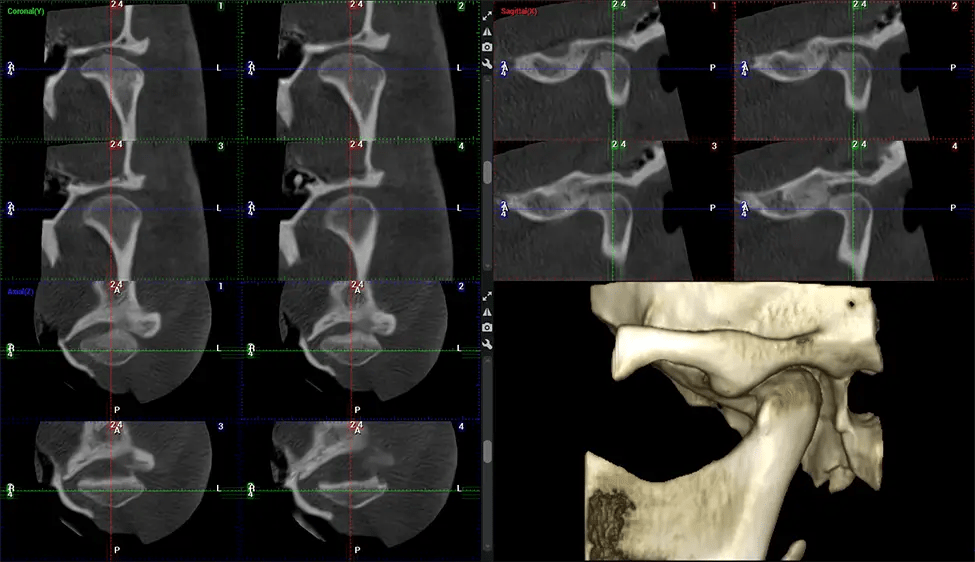

After the scanning process, the captured X-ray images are processed by the CBCT software, which applies algorithms to reconstruct a detailed 3D image of the scanned area. The software compiles these individual X-ray images and creates a digital 3D representation of the patient’s anatomy. The reconstructed 3D CBCT image can be viewed and analyzed by the dentist or radiologist. This image can be manipulated, rotated, and zoomed in or out to examine specific structures and evaluate the patient’s condition.